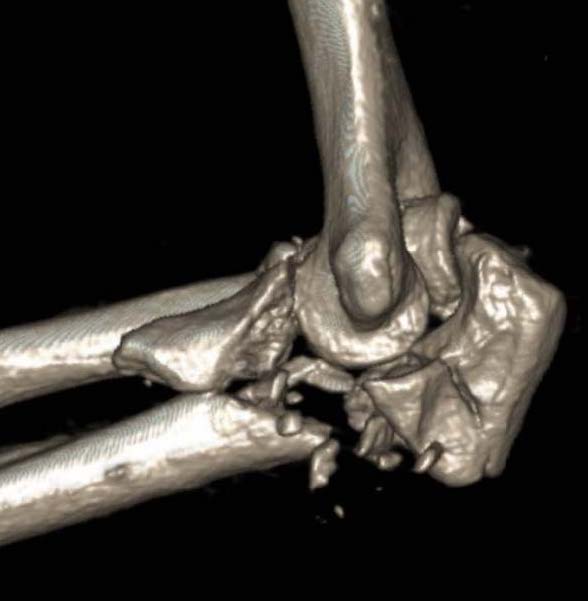

Elbow dislocation + olecranon fracture + radial head/neck fracture +/- coronoid fracture

- 85% coronoid process and 87% radial head fractures

- 5% LCL injuries